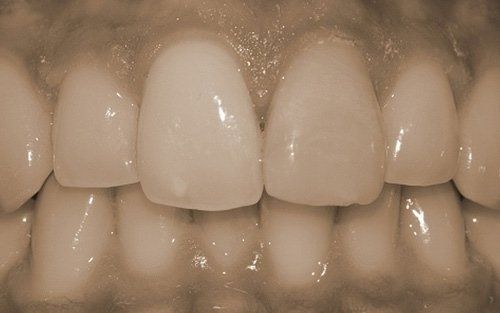

I denti da latte traumatizzati più spesso vanno incontro a necrosi con conseguente cambiamento di colore, divenendo grigiastri, segno della morte delle cellule della polpa dentaria. In altre occasioni, il dente può fratturarsi in maniera più o meno ampia: se il frammento viene ritrovato, potrà essere re-incollato in maniera invisibile, oppure verrà ricostruito con i materiali compositi.